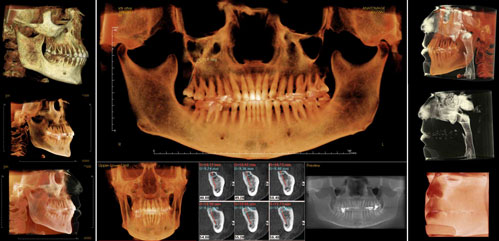

CT Dental Scan Makes Dental Implants Even Better

CT Dental Scan gives us the power to make your dental implant procedure even better. By creating a 3D computer image of your bone structure, CT Dental Scan lets us plan your dental implant surgery precisely before the procedure begins. It’s as if the first part of your surgery is performed on the computer not in your mouth!

Benefits of CT Dental Scan:

- Dental implant procedure can be completed more quickly

- Dental implants can be placed more precisely

- Risk of complications is reduced

- Small incisions can be used with no need for stitches

- Faster healing

- Less discomfort

By taking the place of exploratory dental surgery, CT Dental Scan takes the guesswork out of dental implant surgery, without the need for exploratory cutting. Your dental implant procedure can be done right the first time.